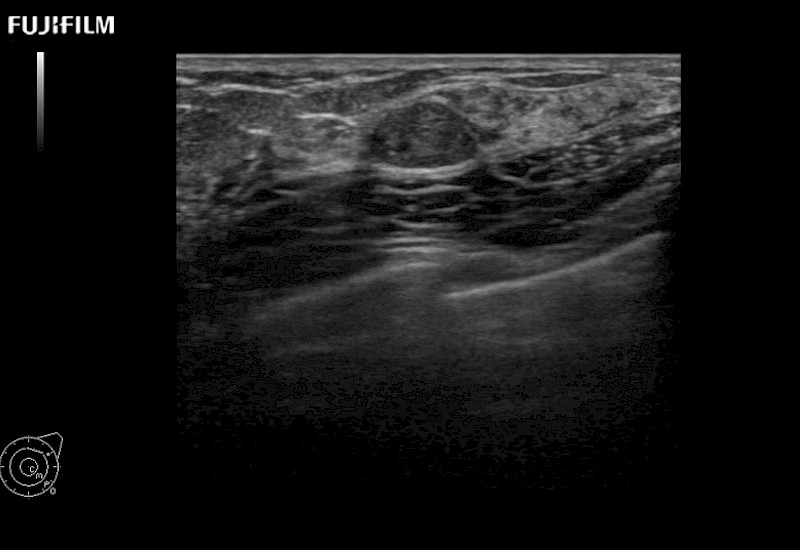

for use during open and laparoscopic procedures: Tumor localization & staging, Ablation, Resection, Biopsy, Transplant, Abdominal exploration, Robotic surgery

Learn moreFujifilm Healthcare continues to listen to the experts, our neurosurgeons, by developing an ultrasound system specifically designed for the Operating Room.

Guidance is the fundamental purpose for all of our surgical ultrasound technology. Fujifilm Healthcare is committed to designing tools that help neurosurgeons navigate inside the human body and provide the necessary information to immediately make critical surgical decisions.

With the ARIETTA Precision the next level of surgical ultrasound is here.